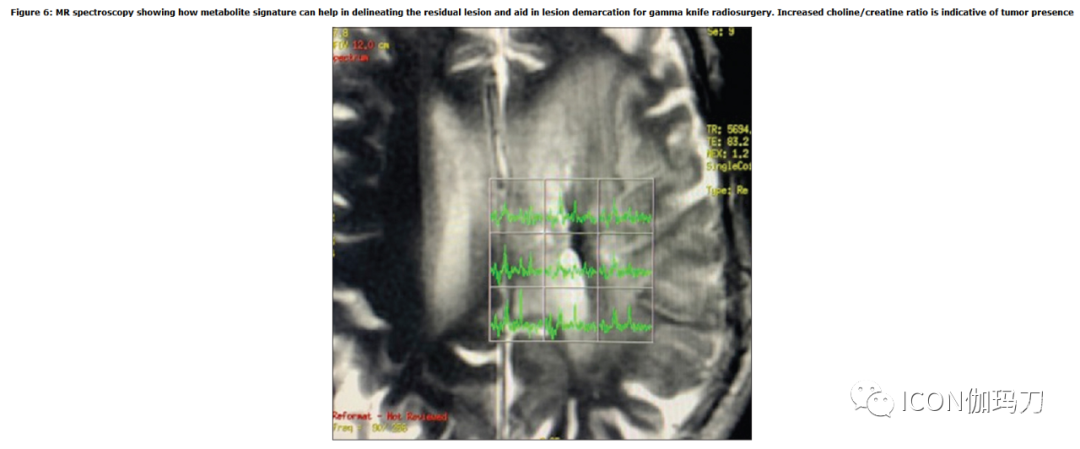

MR波谱学- MR波谱学(MRS)提供肿瘤环境的生化信息。 MRS上常见的代谢物有肌酸,N-乙酰天冬氨酸(NAA),胆碱,脂质,乳酸等,胆碱是髓鞘分解和肿瘤增殖的标志-高胆碱表明肿瘤快速转移,MRS级别较高有助于肿瘤与辐射/手术诱导的变化区分。肿瘤进展通常表现为NAA降低和胆碱水平升高以及脂质/乳酸峰的出现。放射性坏死更常见的表现是由于水代谢的抑制,脂质/乳酸峰值升高在结构信息不充分的情况下,MRS图可以导入并与常规图像联合配准,帮助划定肿瘤边界[图6]。Cho/NAA比值越高,肿瘤分级越高。它还有助于检测MRI增强成像边缘以外的肿瘤浸润。常规MR技术有时难以随访GKRS后这些肿瘤,因为放射性坏死可能类似于肿瘤进展。在此,Cho/NAA比值可能起到拯救作用,也可能指导此类患者的预后。

图6:MR波谱显示代谢物特征如何帮助划定残余损伤,并有助于伽玛刀放射外科中损伤的划界。胆碱/肌酸比值升高表明存在肿瘤